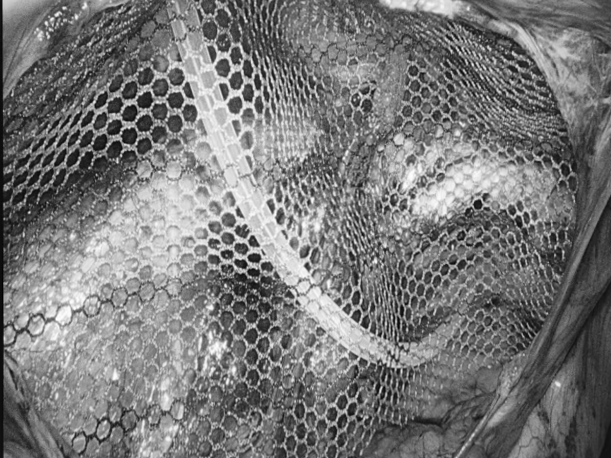

多年来,贵州航天医院各科室紧跟医学前沿,不断强技术、补短板,大力开展新技术、新项目,完成了许多高精尖、高难度、本地区“首例”的技术,填补了医院医疗技术空白,满足了群众日益增长的医疗需求。 本期,我们将为大家带来普外科特色技术——腹腔镜下腹股沟疝无张力修补术(TAPP)。 案例分享 患者在两年前检查发现双侧腹股沟区可复性包块,因当时症状较轻,偶有疼痛,患者未予重视,最近几个月,疼痛愈发频繁,严重影响了工作和生活,故前来我院普外科就诊。科室为患者完善了超声等相关检查后,明确诊断为:双侧腹股沟疝。 在充分与患者进行沟通同意后,制定并成功实施了腹腔镜下腹股沟疝无张力修补术治疗的方案,术中出血量少,术后第三天顺利出院。 腹腔镜下腹股沟疝无张力修补术(TAPP)能在无张力的情况下,利用人工高分子材料网片进行修补,具有术后疼痛轻、恢复快、复发率低等优点,已成为目前患者选择最多的疝修补术。 什么是腹腔镜下腹股沟疝无张力修补术 像用“补丁”补衣服一般,用人体组织兼容的高分子材料进行“补片”,由于不是强行拉合疝洞两边的组织,而是将补片覆盖腹股沟疝的缺损,所以组织间不产生张力,最大限度地保留了人体原有的生理结构和组织层次。同时,补片多呈网状结构,能起到支架作用,使人体自身的组织沿着补片支架生长。 腹腔镜下腹股沟疝无张力修补术原理 通过三个仅0.5 -1cm 的小切口进入腹腔,打开腹膜后将疝囊回纳,利用腹腔镜和专用器械在腹膜前间隙植入补片,覆盖肌耻骨孔,关闭腹膜后完成疝修补操作,有效减小了患者手术创伤。 腹腔镜下腹股沟疝无张力修补术优势 (一)修补结实,损伤更小。 (二)具有符合生理学的优势,术后不适感减少。 (三)保持局部组织结构层次,为再发疝或其他疾病留下治疗余地。 (四)能全面观察病情,发现无明显症状的隐匿疝,避免遗漏。 贵州航天医院普外科专家团队 梁 跃 中共党员,普外科党支部书记、主任,主任医师 临床擅长:对普外科各类肿瘤手术具有丰富的临床经验。 毕业于遵义医学院,遵义市医学会小儿外科学分会常务委员,遵义市肛肠协会理事,遵义市医学会核医学分会(第二届)委员会委员;荣获第三期“黔医人才计划”优秀学员称号;主持市级课题1项,完成省级课题1项,在国内各类刊物上发表论文10余篇。 钱科洪 民盟盟员,普外科副主任医师 临床擅长:从事普外科临床工作30余年,对各类普外科疾病的诊治、乳腺、甲状腺、胃十二指肠、结直肠等疾病及疑难杂症具有丰富的临床经验。 毕业于遵义医学院临床医疗系,2009年前往中山大学附属第一医院微创外科进修学习,在国内各专业期刊发表论文数篇。 贵州航天医院普外科简介 基本情况 贵州航天医院普外科成立于1968年,前身属于航天部O61基地3417医院外一科,1998年3417医院、3427医院合并后更名为普外科,下设胃肠外科、肛肠外科2个亚专业科室,拥有在全市较为先进的专科设备和技术,是中国疝病专科联盟单位,贵州医科大学附属医院胃肠外科专科联盟单位。开放床位40张,配备医护人员21人。 专科特色 普外科致力于胃肠及肛肠疾病的外科临床诊治及科研,以腹腔镜微创外科技术为本,形成以快速康复治疗胃肿瘤、结直肠肿瘤、小肠肿瘤、直肠脱垂、肥胖病、急腹症、各类疝、痔、瘘等专科特色,同时注重胃肠疾病尤其是结直肠恶性肿瘤的基础研究和临床转化研究,总体诊断和治疗水平在区域同级医院居于领先水平。 开展手术:腹腔镜下胃癌根治术,腹腔镜下袖状胃切除术,腹腔镜下胃肠道间质瘤切除术,腹腔镜下结、直肠癌根治术,胃癌、结直肠癌的精准治疗,腹腔镜下小儿疝气、成人疝修补术,腹腔镜下阑尾手术,内痔的硬化注射治疗及痔疮的微创治疗:ATH、PPH、TST,直肠脱垂的各种手术治疗,难治性伤口VSD技术,鼻胃肠管、肠梗阻导管置入术,肛肠术后间歇性导尿技术,并引进了中医适宜技术,也为各种化疗患者提供输液港安装,提高患者就医体验。 腹腔镜下腹股沟疝 无张力修补术 腹股沟疝里金斯坦(Lichtenstein)手术 PPH微创术治疗环状混合痔 黏连性或炎性肠梗阻-肠梗阻导管 腹腔镜袖状胃切除 腹腔镜阑尾切除术 腹腔镜阑尾肿瘤切除术 腹腔镜下结肠癌根治术 诊疗范围 胃肿瘤、结直肠肿瘤、小肠肿瘤、肥胖症、各类急腹症、腹部外伤、腹壁疝、便秘、直肠脱垂、痔疮、肛瘘、肛裂等胃肠、肛肠外科疾病。 一审一校:梁 跃、黄成成